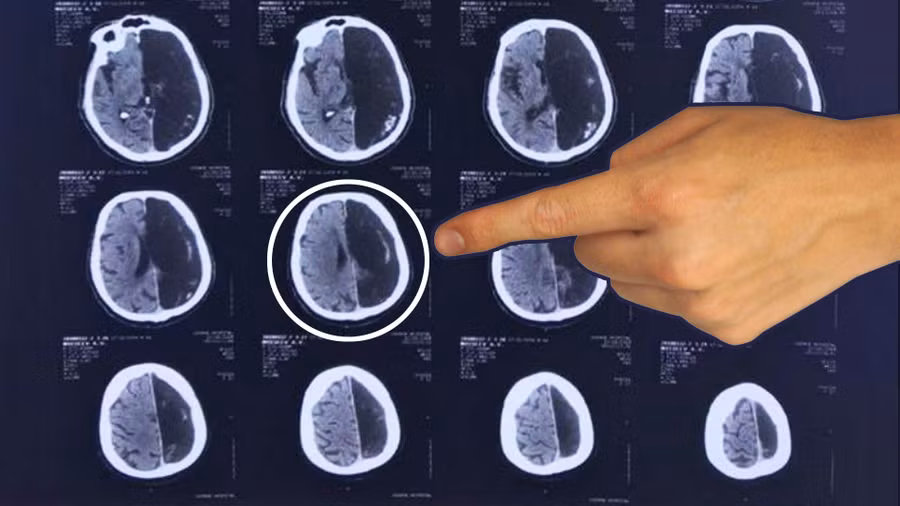

Hình ảnh chụp não của bệnh nhân.

Một trường hợp bệnh nhân ở Moscow đã được bác sĩ phát hiện ra bị mất một nửa bên não theo đúng nghĩa đen. Tuy nhiên, người đàn ông 60 tuổi này vẫn đã và đang sống một cách khỏe mạnh trong hàng chục năm qua mà bản thân không hề biết về tình trạng của mình, tờ RBTH đưa tin.

Nhà thần kinh học giải thích, ở giai đoạn phát triển ban đầu, bộ não con người có thể phân phối lại các chức năng từ bán cầu này sang bán cầu kia vì các chức năng này chưa được neo vào bất kỳ bán cầu não cụ thể nào.

Điều này có nghĩa là mặc dù người đàn ông thiếu một nửa bộ não, ông không có bất kỳ khuyết tật não nào.